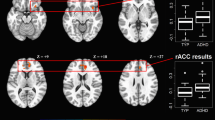

Intrinsic fronto-subcortical FC in girls and boys with attention-deficit/hyperactivity disorder (ADHD) and typically developing (TD) controls. a Topography of fronto-subcortical networks estimated from the functional magnetic resonance imaging data using group-independent component analysis. Components with the strongest spatial correlation with anatomical fronto-subcortical regions of interest (ROIs) are shown. Frontal components include F1 (ventromedial PFC; pink), F2 (anterior cingulate cortex; purple), and F3 (anterior dorsolateral prefrontal cortex; blue). Subcortical components include S1 (striatum; green) and S2 (amygdala/hippocampus; red). b Dot plots and 95% confidence intervals of the intrinsic synchronization of each pair of the participant-specific fronto-subcortical networks for each diagnostic group separately for boys (top) and girls (bottom). Typically developing (TD, n = 75) children are in blue; children with attention-deficit hyperactivity disorder (ADHD, n = 72) are in green. Synchronization was calculated as the Pearson correlation between component time courses and converted to a Z-score using Fisher’s transform. Confidence intervals are based on comparing the mean of each group to 0. Significant diagnostic group differences within sex were observed among girls only (Table 2) in FC of the S1 (striatum) component with all of the prefrontal components and F1-S2 (vmPFC-amygdala components) FC. *Significant effect after FDR correction applied for six tests; †significant effect without FDR correction

Diagnostic group differences in fronto-subcortical functional connectivity

Analyses of between network FC indicated significant effects of diagnosis and diagnosis × sex interactions as shown in Table 2. Children with ADHD showed atypical FC of F1 (vmPFC) with both subcortical components, such that positive FC with S1 (striatum) was greater in ADHD and negative FC with S2 (amygdala/hippocampus) was weaker in ADHD. In addition, children with ADHD showed greater negative FC between F3 (anterior dlPFC) and S1 (striatum) (FDR uncorrected only). Further, there was some evidence of diagnosis × sex interactions for FC of both F3-S1 (anterior dlPFC-striatum components, p = .048) and F1-S2 (anterior dlPFC-amygdala components, p = .042), due to much larger effects in girls (ds = .74 and .94 in girls compared to .01 and .20 in boys), although these interactions did not survive the FDR correction. Given our a priori hypotheses of sex differences in the diagnostic effects, we tested whether fronto-subcortical FC differed between diagnostic groups separately for girls and boys. Examination of post hoc comparisons for girls and boys separately indicated that diagnostic group differences were driven by girls, with greater FC of S1 (striatum component) with all frontal components and weaker F1-S2 (vmPFC-amygdala components; see Fig. 1), whereas no significant diagnostic effects were observed among boys.